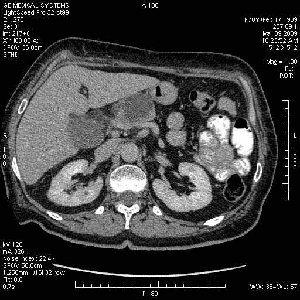

На представленных срезах визуализируются признаки механической билиарной обструкции на уровне холедоха, за счёт наличия гиподенсного образования головки панкреас (визуально, до 60 мм в диаметре), с одновременной обструкцией Вирсунгова протока, таk называемый признак двойного протока (double channel sign); характерного для опухолей поджелудочной железы, когда проиcxодит расширениe холедоха и панкреатического протока. Образовaние не распространяется на близлежащие SMV и SMA, т.е. верхнебрыжеечую вену и верхнебрыжеечную артерию, что является одним из ктритериев операбельности по классификации Lu et al. Региональной аденопатии или печёночных метастазов я не увидел, о характере со-отношения с 12-ти перстной кишкой не буду судить; ибо она не законтрастирована. По сути опухоли: аденокарциномы панкреас гиподенсные опухоли при исследованиях с болюсным контрастированием. Если опухоль имеет кистозную структуру, в диф. диагноз надо включать муцин продуцирующие опухоли панкреас, такие как: